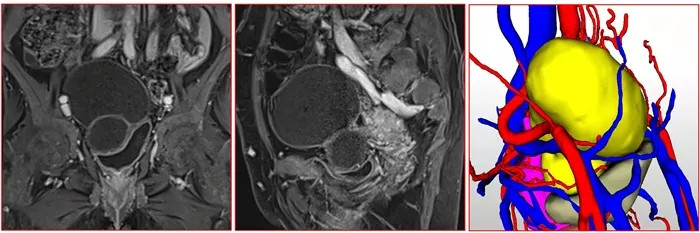

入院后肝膽外科經(jīng)CT、核磁共振檢查發(fā)現(xiàn)肝臟及盆腔有巨大腫塊,考慮肝臟包蟲病、盆腔包蟲病或盆腔畸胎瘤的可能。因病灶與血管關(guān)系密切,盆腔腫塊性質(zhì)待定,需多學(xué)科聯(lián)合會診決定治療方案。

盆腔包蟲病灶